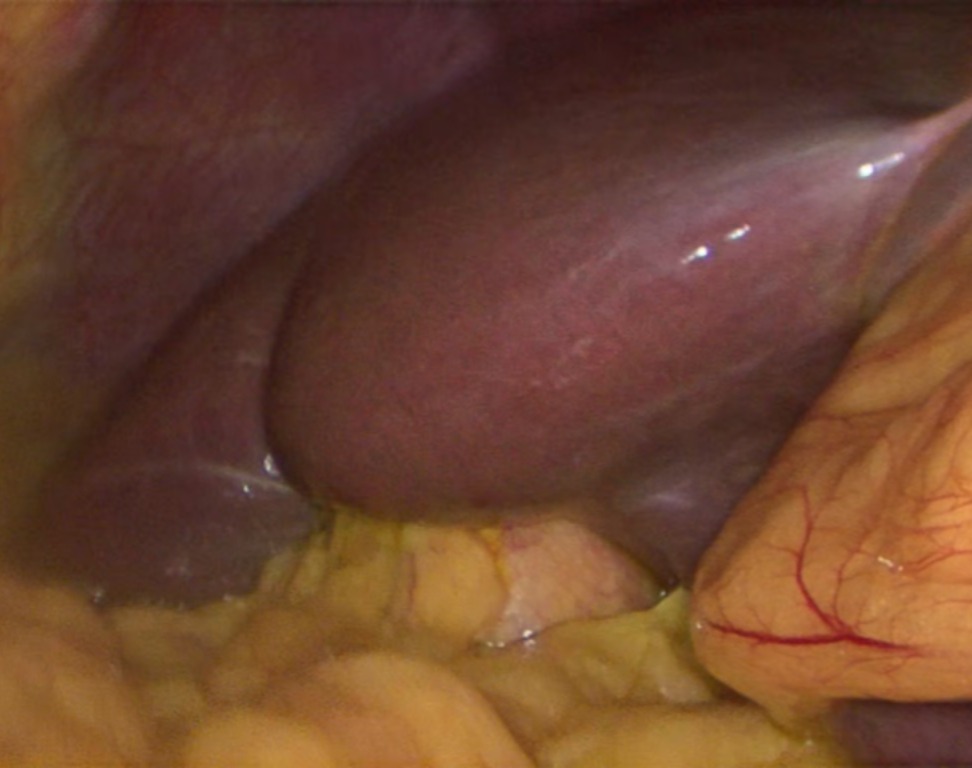

Objetivo: El objetivo de este estudio fue relacionar el signo de fruncido con la colecistectomía difícil, la morbilidad postoperatoria y la escala de Nassar. Métodos: Estudio observacional retrospectivo de casos y controles. Se analizaron los datos de todas las colecistectomías laparoscópicas realizadas en un hospital entre marzo de 2022 y marzo de 2023. Los casos se dividieron en dos grupos según la presencia (LVNC) o ausencia (LVC) de complicación. El grupo LVC se subdividió según la presencia o ausencia del signo del fruncido. Se consideró colecistectomía difícil a las parciales con o sin cierre del cístico, la instrumentación del conducto biliar transcístico, necesidad de colectomía o de derivación bilio digestiva. Variables analizadas: diagnóstico de admisión, procedimientos quirúrgicos realizados, litiasis cística, dificultad para el cierre del muñón del cístico, Nassar, conversión, morbilidad postoperatoria e informe patológico. Resultados: Se realizaron 425 CL durante el período estudiado. El signo del fruncido estuvo presente en 31 del grupo LVC (10%). Se encontró una asociación estadísticamente significativa entre la presencia del signo de fruncido y la necesidad de procedimientos complejos dentro del grupo LVC (p <0,001). Hubo una asociación significativa entre la morbilidad postoperatoria y el signo del fruncido. Discusión: La presencia del signo de fruncido se asoció con un procedimiento quirúrgico complejo, dificultad en el cierre del conducto cístico, morbilidad postoperatoria y conversión. Su presencia fue más común en pacientes mayores sin predilección de sexo. Conclusión: El reconocimiento del signo del fruncido debe alertarnos sobre la posibilidad de una colecistectomía difícil.